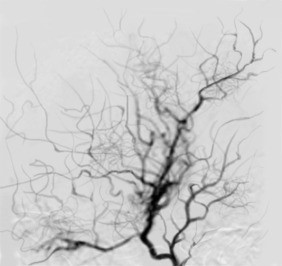

모야모야병이라는 이름은 일본어이다. ‘담배연기가 모락모락 올라가는 모양’이라는 뜻을 갖고 있다. 일본의 의학자 스즈키가 1969년에 붙인 것으로 이 병이 생긴 혈관이 마치 담배연기가 올라가는 모습을 하고 있어 붙은 이름이다.

모야모야병은 동맥 내부의 협착이나 혈관에 이상이 생겨 나타나는 질병으로 소아나 성인 모두에게 생긴다.